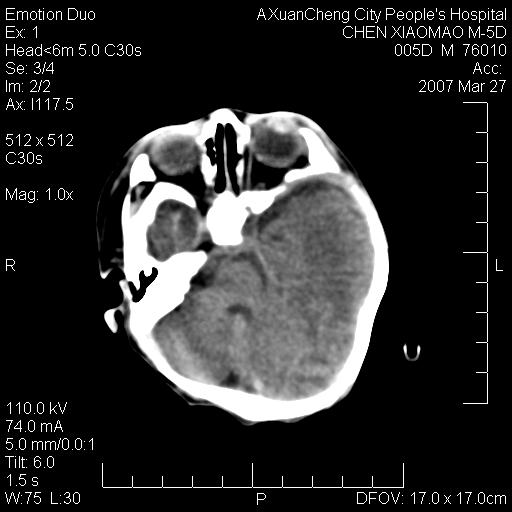

大家看看可有出血?另外枕骨中央是骨缝还是骨折

缝是正常的,但患儿有hie

大家看看可有hie ?还有左侧枕部胡形高密度ct为45~53hu,可有硬膜下血肿?

hie.............

左颞枕部有出血,枕骨有骨折